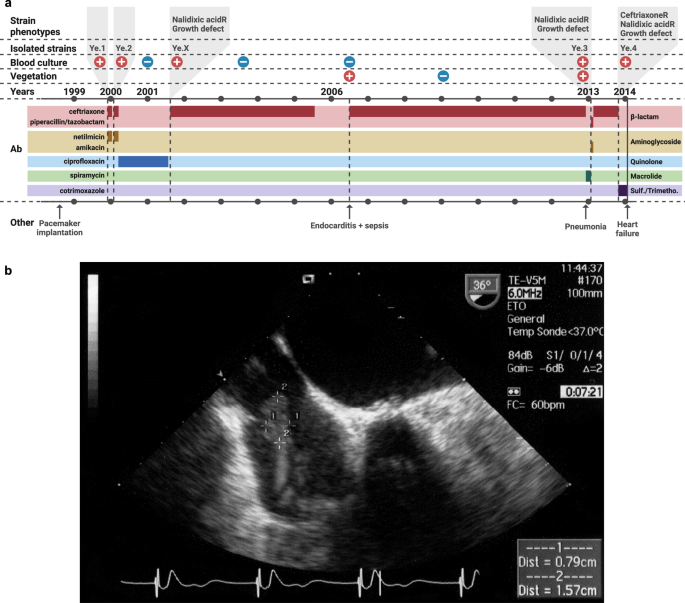

An elderly patient presented with an atrioventricular block that led to a pacemaker implantation in September 1998. In December 1999, the patient had a first septicemic episode resulting in the isolation of a Ye strain (Ye.1) (Fig. 1a). She received ceftriaxone and netilmicin treatment for 4 weeks and recovered. In February 2000, the patient experienced a second episode of bacteremia with isolation of another Ye strain (Ye.2). She was treated with the same antibiotics for four weeks, followed by 18 months of ciprofloxacin therapy (until July 2001), during which monthly blood cultures were negative. A third bacteremia occurred in August 2001 with isolation of a third Ye (Ye.X, not kept in collection) that showed a decreased growth rate, and was resistant to nalidixic acid but susceptible to ciprofloxacin, which had been used for treatment. The patient received a long-term ceftriaxone therapy until July 2005, and monthly blood cultures were negative. In June 2006, the patient was hospitalized for a sepsis but had a negative blood culture. For the first time, echocardiography evidenced vegetations on the pacemaker atrial lead, suggesting endocarditis due to bacterial growth on the cardiac device (Fig. 1b). A 6-year ceftriaxone treatment was administered, leading to vegetation disappearance. In December 2012, the patient suffered from pneumonia, and ceftriaxone treatment was replaced by spiramycin. In January 2013, she presented with another bacteremia with isolation of a fourth Ye strain (Ye.3) and vegetations reappeared on the pacemaker atrial lead. Strain Ye.3, like Ye.X, was resistant to nalidixic acid and showed a severe growth defect. The patient was treated with piperacillin/tazobactam/amikacin for one week, followed by a 9-month ceftriaxone therapy. The patient had a last bacteremia in October 2013, during which a fifth Ye strain (Ye.4) was isolated. Minimum inhibitory concentration (MIC) of ceftriaxone increased from 0.19 mg/L (Ye.3) to 2 mg/L (Ye.4) leading to antimicrobial treatment modification with cotrimoxazole. Three months later, the patient died of heart failure.

a Clinical case description of Ye chronic infection. Positive and negative symbols reflect the blood culture results, or the observation of vegetations on the pacemaker atrial lead. Periods of antibiotics treatment are shown in a darker color on the chronograph, with the associated treatment names on the left and antibiotic classes on the right. Ab: antibiotics. CeftriaxoneR: resistant to ceftriaxone. Nalidixic acidR: resistant to nalidixic acid. Sulf: sulfonamide. Trimetho: Trimethoprim. Created in BioRender. Lê-bury, P. (2025) https://BioRender.com/7nptf49b Vegetation on pacemaker lead. Transesophageal echocardiography performed July 27th, 2006, showing large vegetations on the pacemaker lead in the right atrium. Vegetations formed a sheath around the electrode, measuring 1.6 cm by 0.8 cm.